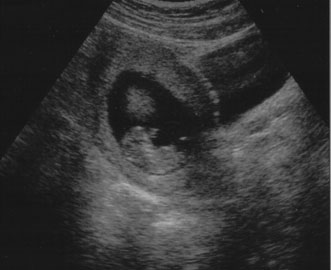

Diagnostic ultrasound is widely used in the assessment of pregnancy and the fetus. Although clinical benefits of routine ultrasonography during pregnancy have not been established, approximately 70% of pregnancies in the United States undergo ultrasound evaluation.30 Because most instruments used in diagnostic ultrasonography produce energies no greater than 10 to 20 mW cm2 (safety defined as less than 100 mW cm2), ultrasound is considered generally safe. No harmful biologic effects on instrument operators, pregnant women, fetuses, or other patients have been found. Infants exposed in utero have shown no significant differences in birth weight or length, childhood growth, cognitive function, acoustic or visual ability, or rates of neurologic deficits (see Fig. 6).

Fig. 6. A: First-trimester twin intrauterine gestations. Ultrasound examination of the pregnant uterus (arrowheads) shows the “owl eyes” characteristic of early twin pregnancies. B: Maternal urinary bladder. (Courtesy of Alfred B. Kurtz, MD)

Fetal number (Fig. 6)